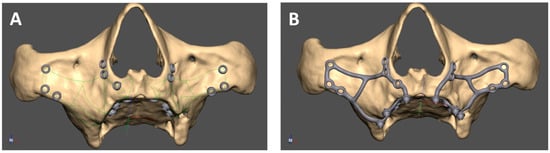

2.3. Mai Implant® Design

The manufacturing center gets in contact with the practitioner with a view to designing the Mai Implant®. The first thing the bioengineer does is import and analyze the bone model in an .STL file in Geomagic Freeform Plus®. Then, the implant mesh is designed in an .STL file. Holes for screws in areas where the bone is sufficiently thick are designed. After the modeling of implant meshes and placement of multiunits in appropriate positions, finishing, contouring, and adjustments of the implant to the bone are performed [Figure 4]. Then, an .STL file of the Mai Implants® is exported.

Figure 4. (A) Mai Implant® with holes where the bone is sufficiently thick. (B) Holes linked with connectors and the placement of multiunits in Mai Implant®.